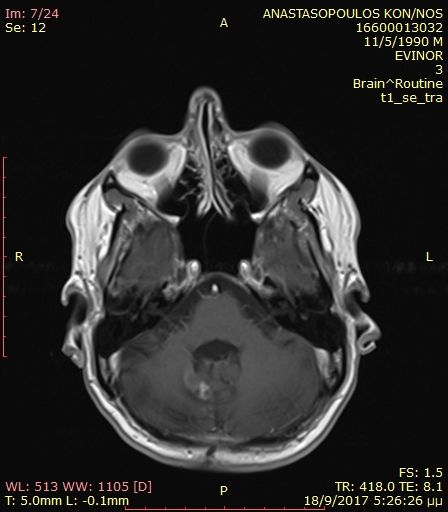

Preoperative cerebellar haemangioblastoma.

Postoperative cerebellar haemangioblastoma after total removal.